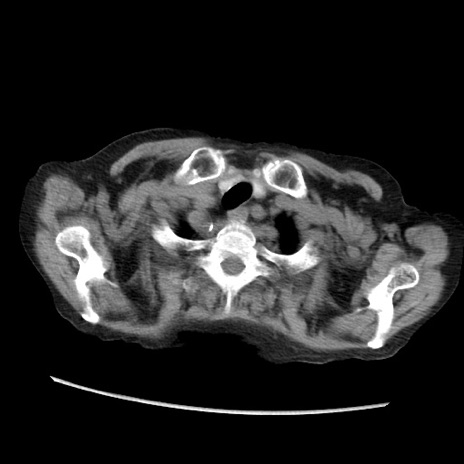

症例31(横断像)

【症例】80歳代 女性

【主訴】腹部膨満感

【現病歴】他院にて肝硬変にてフォロー中。1週間前から便秘、腹部膨満感、臍部腫瘤あり受診となる。

【既往歴】肝硬変

【身体所見】腹部膨隆あり、皮膚変化なし、疼痛なし。

【データ】WBC 4600、CRP 0.25